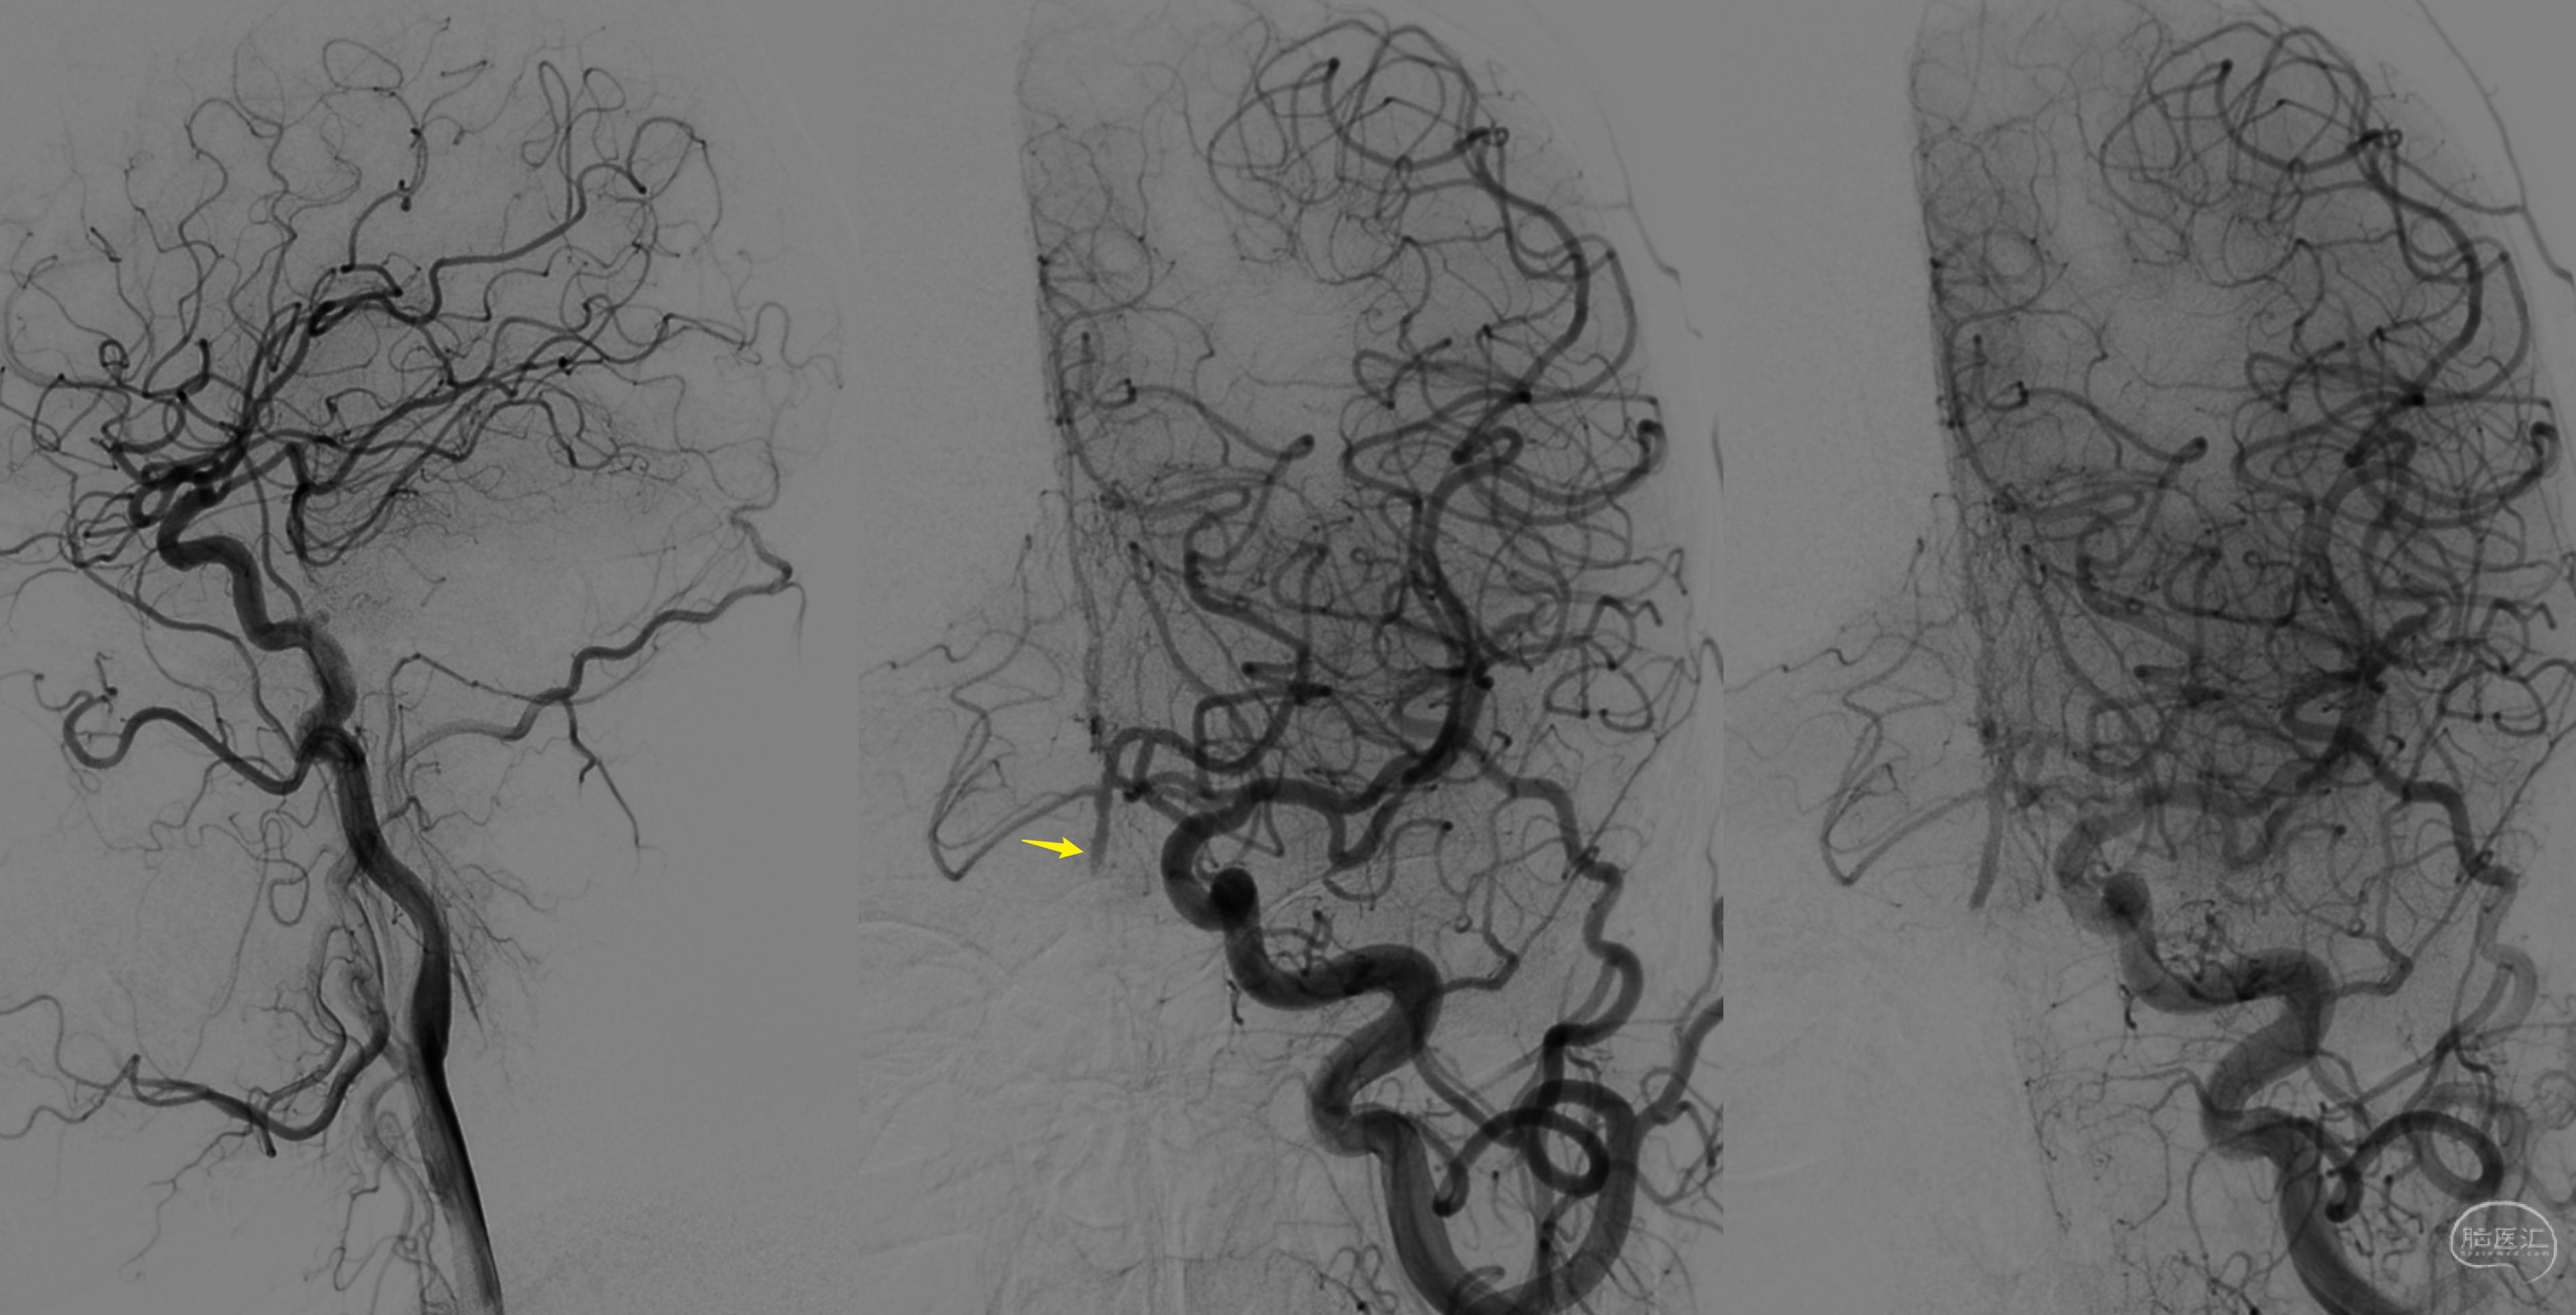

复查DSA造影,提示桥血管通畅,后循环血流明显改善!

三维重建,提示骨性结构完好,OA-V3桥血管通畅,吻合口无狭窄。超声提示血流量33ml/min。

患者恢复顺利,如期出院!电话随访,头晕症状明显改善。